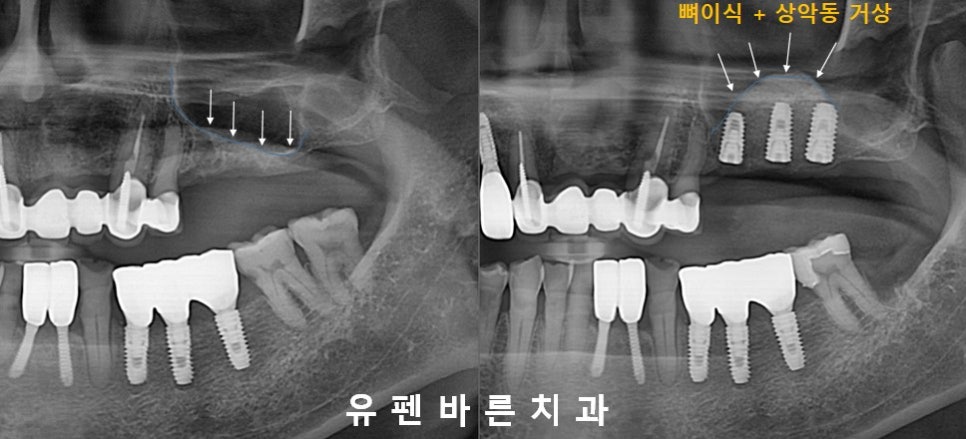

(두번째 케이스)

위 환자분의 경우에도

어금니가 상실되고

상악동 막이 아래쪽으로 내려오면서

임플란트를 식립하기에

뼈높이가 많이

부족한 상태셨습니다. ㅠ.ㅠ

눈으로만 봐도 잔존뼈 높이는

2-3mm정도밖에 되보이지 않습니다.

상악동 거상 과

충분한 양의 뼈이식을 통해

잠실새내임플란트 식립을

잘 마치셨는데요 :)

반구형 모양의

동그랗게 뼈이식이

예쁘게 된 모습이

보이시나요? ㅎㅎ

Sinus Augmentation Teeth No. 13,14,15